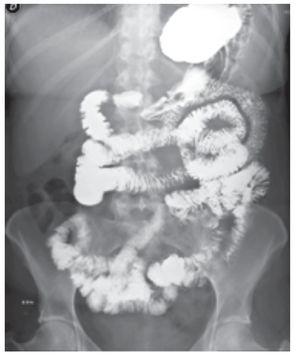

Se le realizó gastroscopia y colonoscopia que mostraron gastritis erosiva antral y duodenitis leve, así como enfermedad diverticular de colon no complicada, un pólipo en colon transverso y tres pólipos a nivel de colon sigmoides, realizándose polipectomía con recuperación de las lesiones para análisis histopatológico (Figura 2). Se tomaron biopsias complementarias del duodeno y diversos segmentos del colon que mostraron la presencia de macrófagos subepiteliales positivos a la tinción de ácido peryodico de Schiff (PAS) y negativa a la tinción de Ziehl-Nielsen, compatible con enfermedad de Whipple (Figura 3). Se modificó el tratamiento iniciando ceftriaxona por vía intravenosa durante dos semanas con desaparición de la diarrea a las 24 horas de haber iniciado el manejo. Egresó con doxiciclina y se mantuvo en vigilancia durante seis meses, durante los cuales estuvo asintomática.

¿ Figura 2. Antro gástrico; presencia de imagen erosiva.